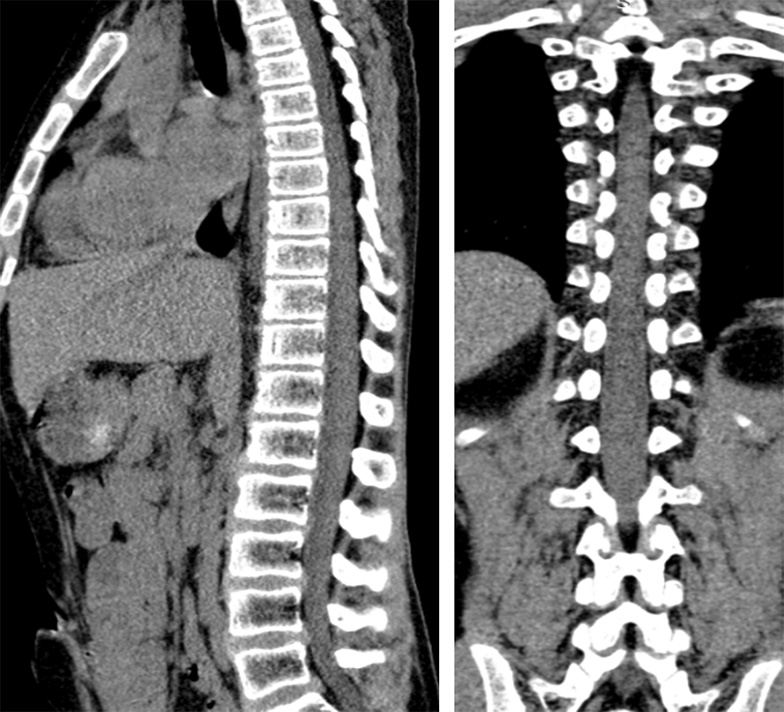

По данным лабораторных исследований клинический анализ крови, биохимический анализ крови, общий анализ мочи без патологических изменений. На компьютерной и магнитно-резонансной томограммах грудного и поясничного отделов позвоночника патологических изменений не выявлено (рис. 5, 6).

Рис. 6. Компьютерная томограмма грудного и поясничного отделов позвоночника в сагиттальной и коронарной проекциях

Рис. 5. Магнитно-резонансная томограмма грудного и поясничного отделов позвоночника в сагиттальной проекции, режимы Т1 ВИ, Т2 ВИ